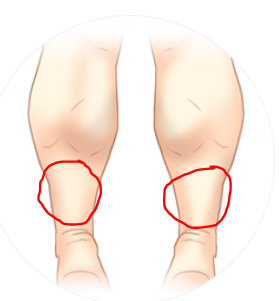

팔, 다리

-힘 빠짐

:종아리, 어깨 등 부위는 주입 위치에 따라 힘이 심하게 빠질 수 있습니다.

종아리 보톡스 역시, 종아리 근육 부위가 아닌 그 아래쪽(빨간 원)으로 주입될 경우 다리에 힘이 빠져 걷기 힘들어질 수 있습니다. 시술받은 후 20분 정도 가볍게 걸어 보톡스가 잘 퍼지게 해야 하며, 무리한 하체 운동은 자제해야 합니다.